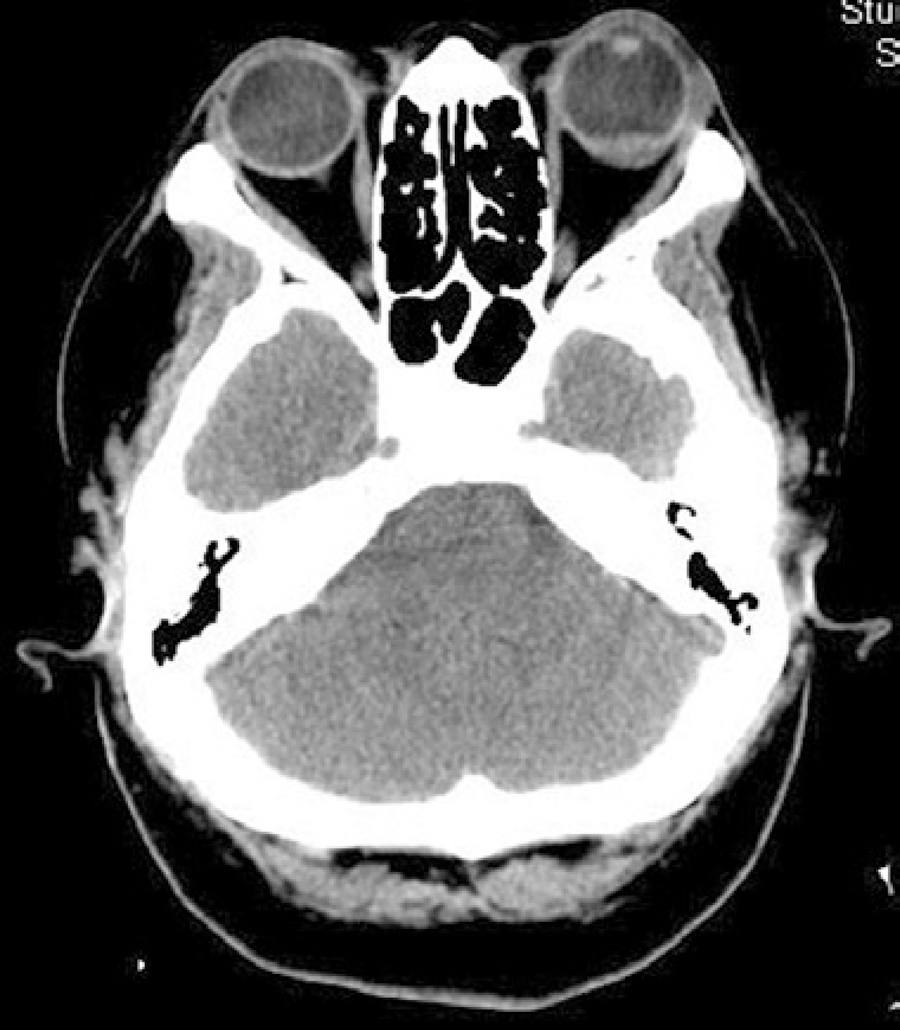

Orbital computerized tomography (CT) scan and magnetic resonance imaging revealed a left eye choroidal and transscleral mass spreading to the Tenon's space, along with thickening of the optic papilla (Figure 1).

The patient was treated for posterior scleritis with oral prednisolone 1 mg/kg body weight once daily. After 2 weeks of treatment, an improvement in pain was noted by the patient, along with BCVA of 6/60 in the left eye with improvement of the macular OCT edema; however, on fundoscopy, worsening of the optic disc edema was found. The orbital CT scan and B-scan ultrasonography revealed identical results. Etiological investigation showed negative anti-HIV antibody test, C-reactive protein level of 0.3 mg/dL, elevated sedimentation rate (59 mm), negative rapid plasma reagin and treponema pallidum hemagglutination test, normal angiotensin-converting enzyme (25 UI/L), negative cytoplasmic and perinuclear anti-neutrophil cytoplasmic antibodies, negative Borrelia burgdorferi and Toxoplasma gondii IgG and IgM, and negative rheumatoid factor and antinuclear antibodies. The chest radiograph was normal and the patient denied any respiratory symptoms or recent travel in TB-endemic regions. The patient had a positive result for the purified protein derivative (PPD) skin test (17 mm induration under corticotherapy 80 mg/day) and interferon-gamma release assay (IGRA), which is a more specific test. Antitubercular chemotherapy was started in combination with the oral corticosteroids, and was a combination of rifampicin 10 mg/kg, isoniazid 5 mg/kg, and pyrazinamide 25 mg/kg. The oral prednisolone treatment was given for 10 weeks, and the antitubercular therapy for 9 months. After 10 weeks of treatment, the patient recovered a visual acuity of 6/6 in the left eye, the optic disc edema and choroidal folds disappeared, and the orbital CT scan (Figure 4) and B-scan ultrasonography were normal. The patient has since remained asymptomatic for a period of 18 months.